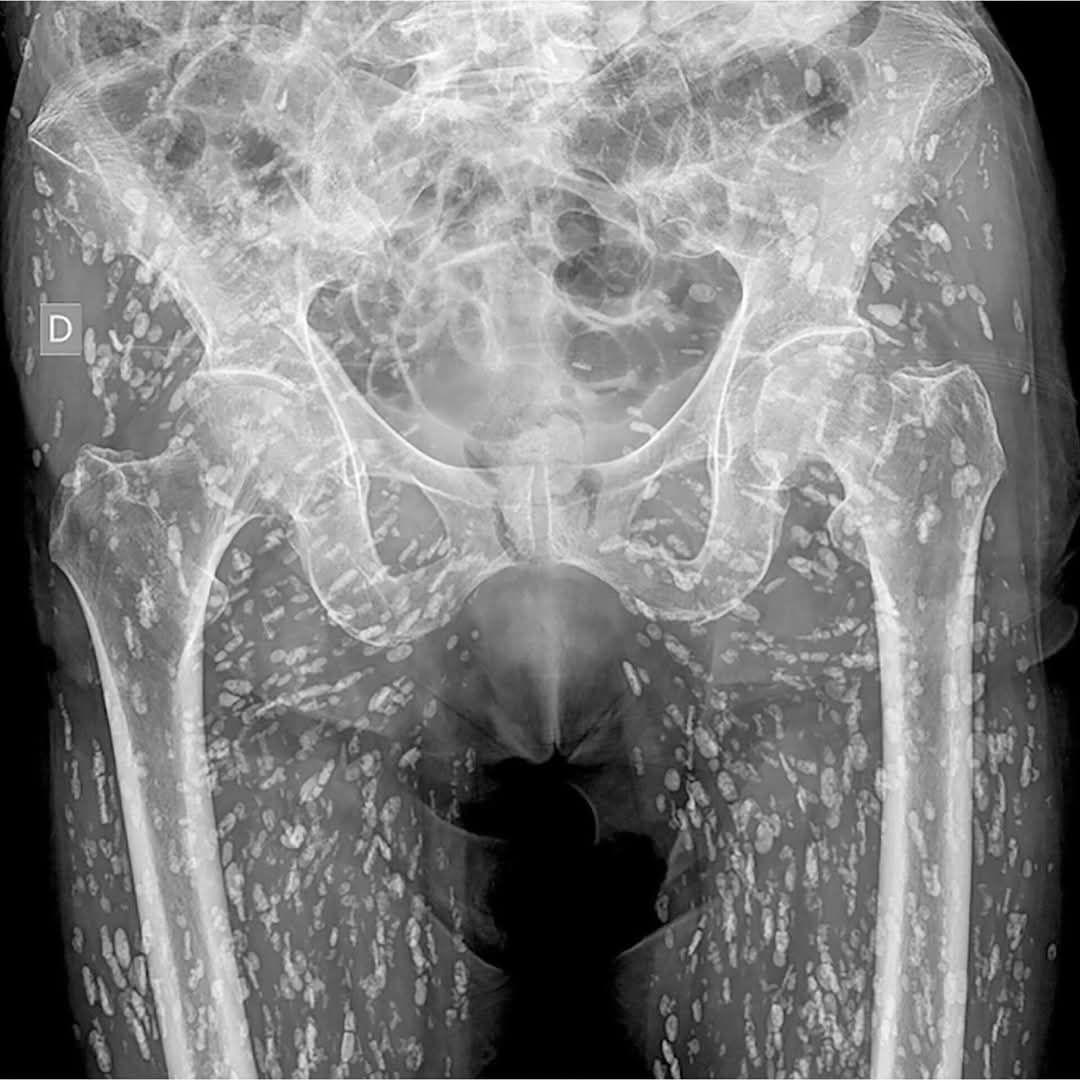

根據媒體《Khaosod》的報導,一名泰國網友「Ai Jaeo Mueang Chan」在臉書分享,自己過去在擔任X光助理時,一名婦人到診所拍攝從髖部到腿部的X光,結果影像一出來佈滿詭異陰影,放射科醫師一看,指出這些白點其實全是寄生蟲!他直言,當時的畫面就像下圖:

示意圖非當事人。圖片來源 / 翻攝自臉書 (Ai Jaeo Mueang Chan)

醫師推測這患者疑似是長期吃生食、生肉,這才間接將寄生蟲的蟲卵或幼蟲吃下肚。在場醫護人員聽了全都嚇傻,看著全身都是寄生蟲的X光,有人狂起雞皮疙瘩,有人則是不斷用酒精洗手。